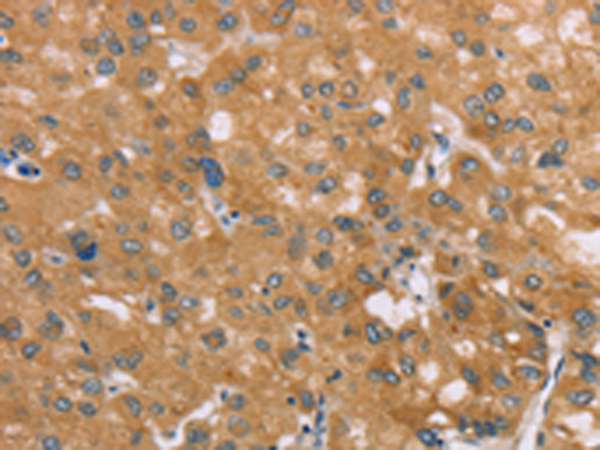

分类: 科研抗体货号: P12146别名: SEI1; TRIPBR1; TRIP-Br1应用: IHC反应种属: Human, Mouse